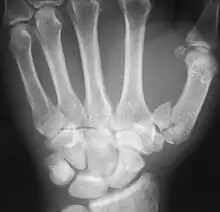

The first metacarpal bone or the metacarpal bone of the thumb is the first bone proximal to the thumb. It is connected to the trapezium of the carpus at the first carpometacarpal joint and to the proximal thumb phalanx at the first metacarpophalangeal joint.

The first metacarpal bone is short and thick with a shaft thicker and broader than those of the other metacarpal bones. Its narrow shaft connects its widened base and rounded head; the former consisting of a thick cortical bone surrounding the open medullary canal; the latter two consisting of cancellous bone surrounded by a thin cortical shell. [1]

The head is less rounded and less spherical than those of the other metacarpals, making it better suited for a hinge-like articulation.

The distal articular surface is quadrilateral, wide, and flat; thicker and broader transversely and extends much further palmarly than dorsally. On the palmar aspect of the articular surface there is a pair of eminences or tubercles which articulate with the radial and ulnar sesamoid bones of the thumb metacarpophalangeal joint; the lateral eminence is larger than the medial.

The body or shaft is thick and broad — averaging 6 to 11 millimetres (0.24 to 0.43 in). On its dorsal side, the shaft is flat and wide, while the anteroposterior side is less pronounced; usually resulting in an oval-triangular cross-section.

The dorsal surface of the shaft is weakly convex longitudinally, while its palmar, radial, and ulnar surfaces tend to be concave. The palmar and medial surface exhibits a blunt ridge which separates a larger lateral part – the insertion of the opponens pollicis muscle – and a smaller medial part – the origin of the lateral head of the first dorsal interosseous muscle.

Base

The base is significantly different from the bases of the other metacarpals. It is trumpet-shaped and ends in a saddle-shaped articular surface matching that of the trapezial articular surface. The configuration of the thumb carpometacarpal joint plays an important role in the mechanism of opposition. The articular surface is delimited by a thick, crest-like ridge extending around its circumference.

On the palmar and lateral side of the base is the insertion of the tendon of the abductor pollicis longus muscle, usually featuring a small tubercle. The origin of the first dorsal interosseous muscle is on the ulnar aspect of the base, and can sometimes extend onto the shaft. In contrast to the other metacarpals, the first metacarpal has no articular facets on the sides of its base (for intermetacarpal articulations) because it articulates exclusively with the trapezium.